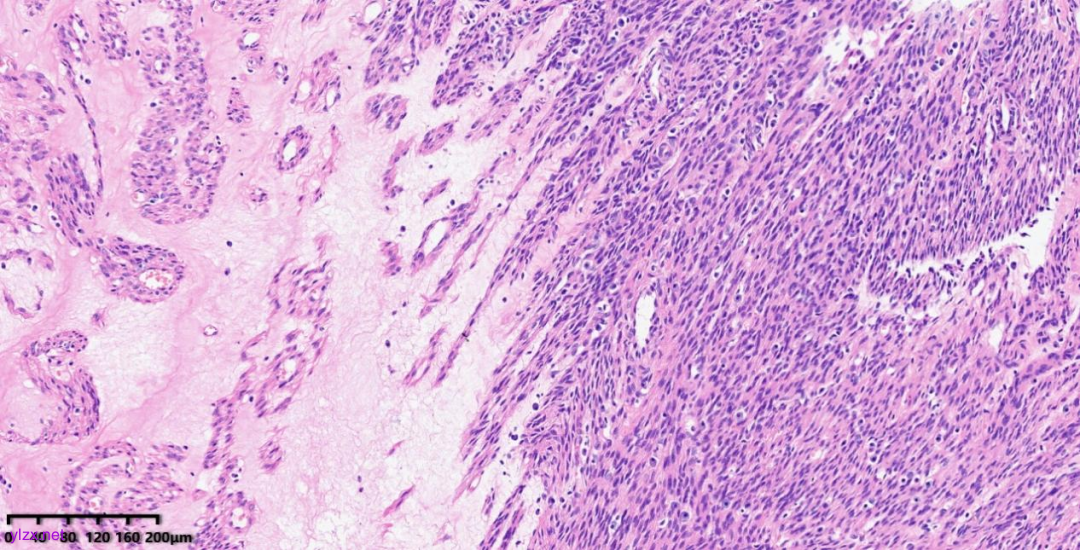

肿瘤细胞以梭形细胞、卵圆形细胞为主,部分为胞浆透亮的上皮样形态,透亮细胞界限较清,胞质淡染或胞浆丰富、嗜酸性,肿瘤内血管丰富,肿瘤细胞围绕血管周围片巢状、束状及放射状排列;肿瘤细胞核异型性不明显,核分裂像少见(<1个/50HPF),染色质开放,可见小核仁;肿瘤间质水肿、黏液变性,纤维胶原增生伴玻璃样变性。

图1~5 低倍镜下:肿瘤细胞以梭形细胞、卵圆形细胞为主,部分为胞浆透亮的上皮样形态,肿瘤细胞分布疏密不均,部分区密集丰富,部分区肿瘤细胞稀少,间质疏松水肿、黏液变性,肿瘤细胞围绕血管周围生长,局部间质纤维胶原增生伴玻璃样变性。

图6 中倍镜下:肿瘤内血管丰富,胞浆透亮的上皮样细胞围绕血管周围片巢状、束状及放射状排列。